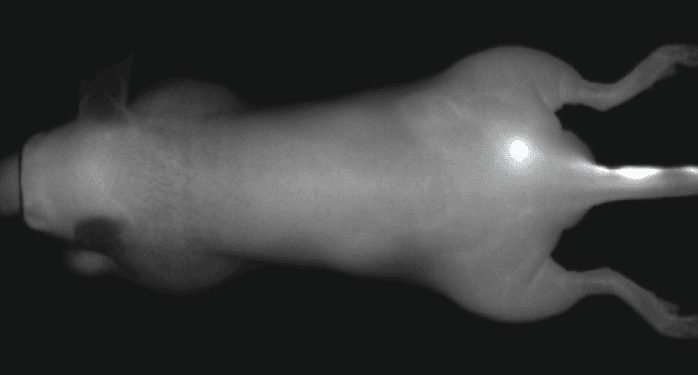

An NIR dye-conjugated contrast agent, such as IRDye 800CW PEG (polyethylene glycol), serves as a non-specific contrast agent for vascular imaging. The labeled agent is administered to mice intravenously (IV injection) and highlights surface vasculature for 30 minutes post-injection (Figure 6). The retention of the agent is visible in the tumor 4 hours post-injection (Figures 7A, B; requires appropriate mouse model*) and the tumor region is defined by 9 hours post-injection (Figure 8).

*Success of vascular imaging depends on the mouse model used. Vessels may be less visible in mice that are obese or have hair.